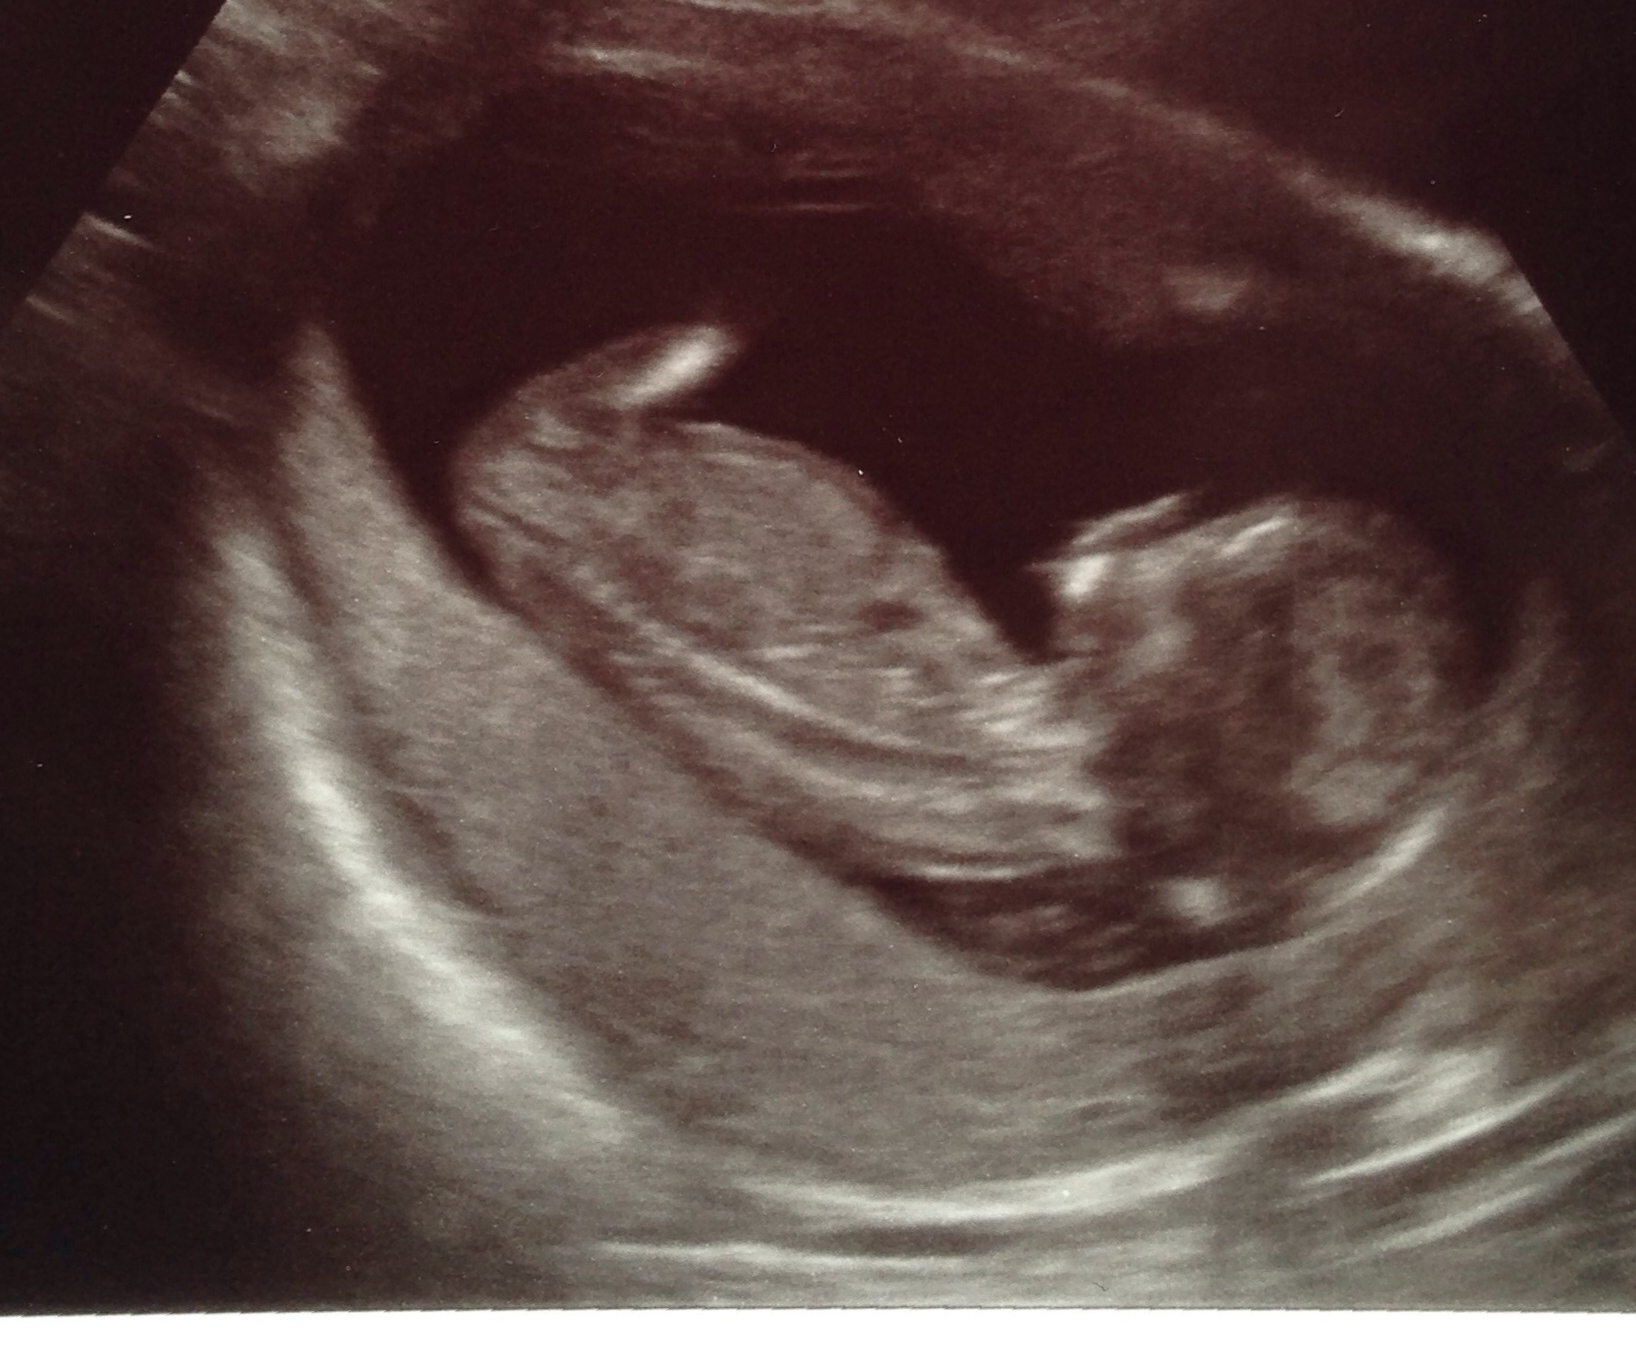

April 22, 2014: BFP! beta #1: 80 beta #2: 211 One nugget!